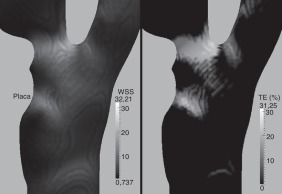

Los resultados del muestran (fig. 6 , sup.) valores altos de 37,76 Pa en el modelo A en la bifurcación y próximos a 20 Pa en los otros 2 modelos, siendo ligeramente más acentuados en el modelo B que en el C. En cuanto a los TE para WSS superiores a 30 Pa (fig. 6 , inf.) son más altos y abarcan una zona más extensa en el modelo A que en los modelos B y C. Estos valores de y del TE suponen, como ya se ha dicho, un riesgo de ulceración, trombosis y rompimiento posterior de placa. Por tanto, el modelo A implica un riesgo de embolización superior a los modelos B y C, siendo el B ligeramente superior al de C.

Carótidas idealizadas. Arriba: WSS¯ en Pa. Abajo: TE correspondiente a un WSS ...

Figura 6.

Carótidas idealizadas. Arriba: en Pa. Abajo: TE correspondiente a un WSS superior a 30 Pa, en porcentaje del período.